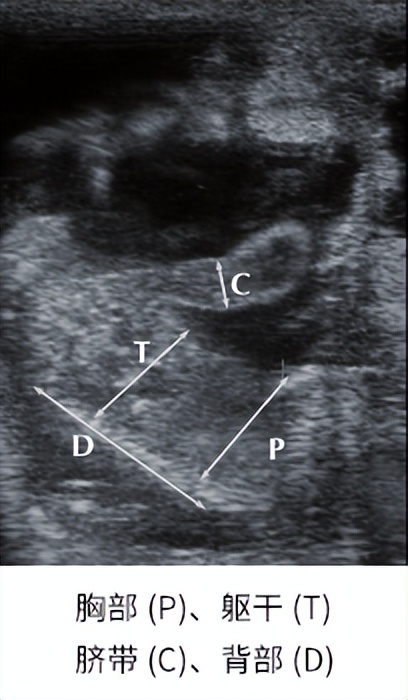

使用羊用B超机确定妊娠母羊胎龄可以为饲养管理、预期产犊提供便利。母羊妊娠胎龄的确定基于胚胎和胎儿尺寸的测量,如胚胎囊泡直径、胚胎长度、长骨长度(胫骨、股骨、肱骨、尺骨或桡骨)、双层直径、胸径、胎儿心率,胎盘直径和眼腔直径(看下图)。

在妊娠第 42 天到第 150 天之间,通过超声波可以轻松识别脐带。 脐带直径与妊娠阶段高度相关(R 2 > 0.90)。 作为妊娠末期胎儿变大时测量腹径的基准。 在脐部测量腹部直径具有简单且与妊娠阶段相关性非常好的优点(R 2 ≥ 0.96)。